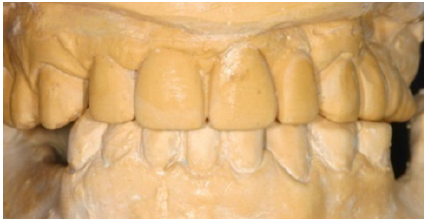

Initial alginate impressions were taken for the fabrication of initial study casts. Prior to jaw registrations an initial occlusal splint was fabricated and given to the patient in order to reduce TMJ symptoms (Figure 7). Using a transparent 2mm hard plate after thermal processing and vacuum on maxillary study cast a retentive basis was fabricated. The splint was fabricated chairside by adding autocuring acrylic resin (Jet, Lang, USA) and after occlusal reduction the increase of VDO was set to 5mm. Two weeks later a face bow registration (Hanau) and three centric relation registrations were taken to ensure the accuracy of the procedure. (Figure 8). Study casts were mounted in a semi adjustable articulator (Hanau H2). The static occlusion analysis revealed increased vertical overlap, and a discrepancy of occlusal plane in quadrant #1 (Figure 9).

Figure 9: Study casts (frontal view).

The diagnostic wax-up was performed in an increased vertical dimension of occlusion (approximately by 3mm). The maxillary teeth were imposed in minimal modifications; however the diastemma between #13 and 15 was difficult to be eliminated. The increase in VDO was mainly attributed to the mandibular teeth in order to alter frontal abraded dentition and to create the important prosthetic space for the posterior missing teeth. The existent prosthetic restorations in the maxilla were slightly differentiated in the wax up, however significant occlusal reduction was performed in teeth #15 and #16 (Figure 4 & 10). These modifications corrected occlusal plane.